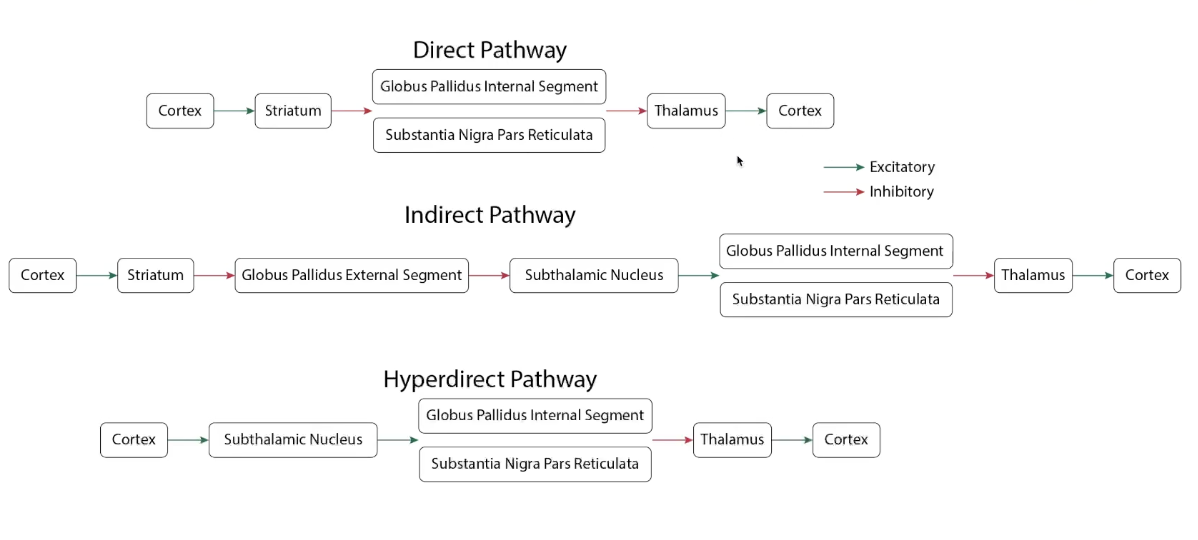

Indirect & Direct Pathways

Indirect pathway inhibits the subthalmaus and supresses signalling through the thalamus and movement

Direct pathway disinhibits thalamus making it easier to fire